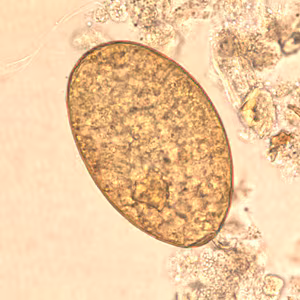

Fasciolopsis buski eggs.

Microscopic identification of eggs, or more rarely of the adult flukes, in the stool or vomitus is the basis of specific diagnosis. The eggs are indistinguishable from those of Fasciola hepatica.